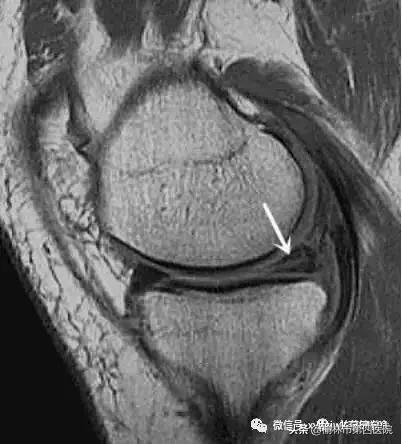

半月板的破裂类型:

2、磁共振上显示Ⅲ度以下的半月板损伤可暂先保守治疗。